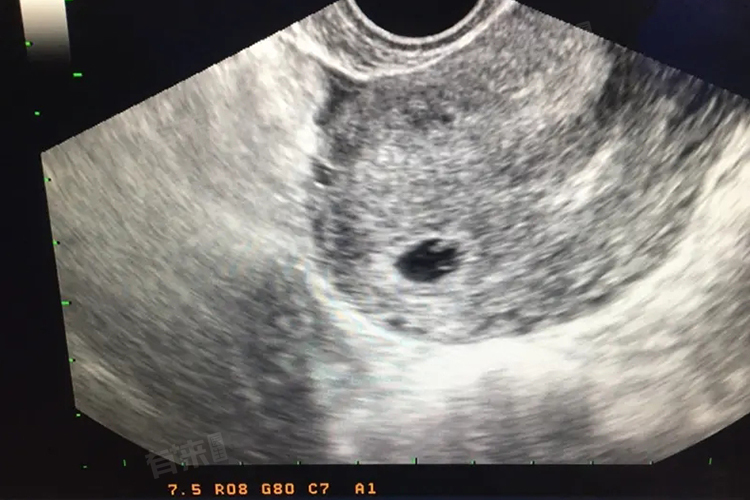

怀空囊是指在怀孕早期,超声检查发现孕囊内未见胎芽、胎心等胚胎组织,仅是一个空的孕囊结构,年龄偏大的女性、内分泌失调的女性、有生殖系统感染病史的女性等相对更容易出现这种情况。

- 出现疑似怀空囊的情况后,应选择更专业、权威的医疗机构,通过更精密的超声仪器再次进行检查,同时结合血液中相关激素水平的检测结果综合判断。因为有可能存在检查误差,比如超声检查时间过早,胚胎尚未发育到能被清晰观测到胎芽、胎心的阶段,或者检测设备、操作医生的经验等因素影响了诊断结果,所以需要先确认诊断的准确性。